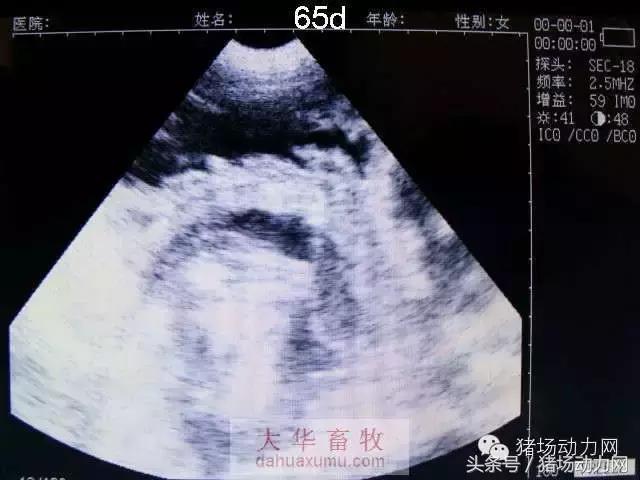

以下为怀孕母猪21天到90天之内的变化图:

65天